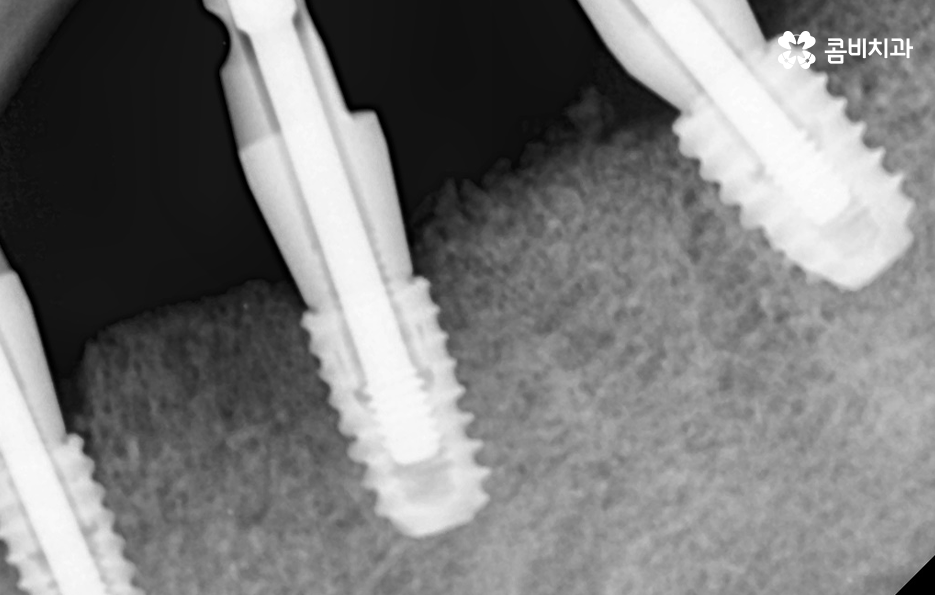

뼈이식이라고 하면 아무래도 어떤 뼈를 이식한다는 것인지 어렵게 느껴지기 쉬운데 일반적으로 치과 임플란트 뼈이식에 사용되는 뼈의 형태는 가루 상태의 뼈를 반죽 처럼 만들어서 잇몸 뼈에 이식한다고 이해하시면 되는데 뼈이식이라고 해서 통증이나 출혈이 더 심해지거나 그런 것은 아니기 때문에 너무 우려하실 필요는 없다고 볼 수 있어요

임플란트 시술 전과 후에는 모두 임플란트 치조골 상태의 중요성이 무척이나 크며 시술의 성공률에도 크게 중요하며 시술 후 수명 유지를 좌우할 정도 임플란트 치료에 있어서 치조골의 상태는 무척이나 중요하다고 이해하시면 좋을 거예요